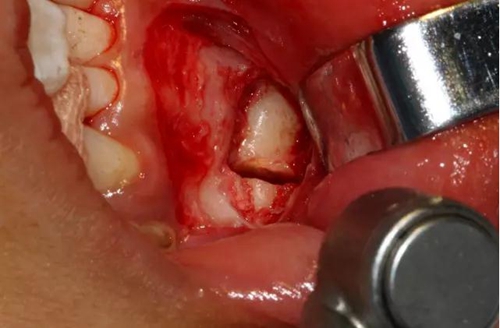

橫斷牙冠,注意深度的把控

為了減少骨創(chuàng),“T”型分割牙冠

去除冠部